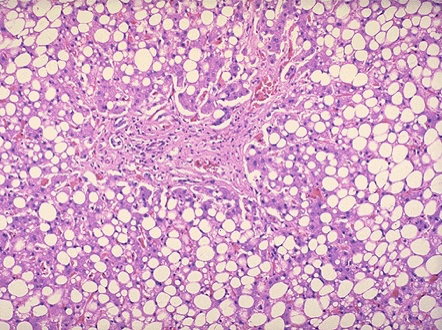

(3)脂肪变性:肝细胞脂肪变性常发生在丙型肝炎。

病理变化:肉眼观,肝体积显著缩小,尤以左叶为甚,重量减至600~800g,质地柔软,表面被膜皱缩。切面呈黄*色或红褐色,有的区域呈红黄相间的斑纹状,故又称急性黄*色肝萎缩或急性红色肝萎缩。镜下见肝细胞呈一次性大块坏死(坏死面积≥肝实质的2/3)或亚大块坏死。肝索解离,肝细胞溶解,仅小叶周边部残留少数变性的肝细胞。肝窦明显扩张充血并出血,库普弗细胞增生肥大,并吞噬细胞碎屑及色素。小叶内及门管区有淋巴细胞和巨噬细胞为主的炎细胞浸润。残留的肝细胞再生现象不明显。